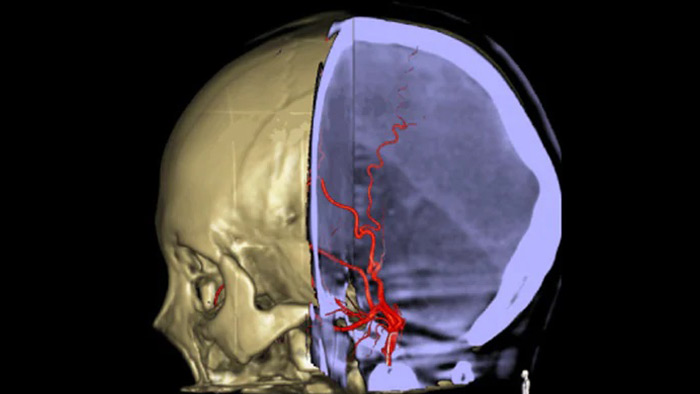

SmartCT Vasoでは、脳梗塞の梗塞部位の全体像を可視化することができる撮影機能です。SmartCT Vasoは、動脈への造影コーンビームCTに高分解能撮影の技術を組み合わせた撮影技術でrestrictive fillingによる梗塞部位の遠位血管も描出することができ、血栓の位置、長さ、梗塞部位の全体像を視覚化できます。3Dロードマップを組み合わせて使用することにより、術中の血栓回収デバイスのナビゲーションも可能となります。

SmartCT Roadmapでは、ガイドワイヤ、カテーテル、およびデバイスの正確なナビゲーションをサポートする解剖学的なリファレンスを提供します。